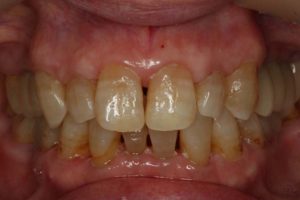

どのように変わったか、下の写真をご覧ください。

長い間お疲れ様でした。この患者さんは、奥歯を何本も失っていて満足なお食事ができない状態でした。前歯も所々虫歯で黒ずんでいて気になって口を開けて笑えないとおっしゃっていました。そもそも、最初はお嬢様の結婚の前までに綺麗にしたいというものだったのですが、治療をしていくうちに奥歯の大切さを実感していただいたようです。

奥歯にインプラントを入れ、前歯はホワイトニングやダイレクトボンディング、セラミックなどで修復しました。